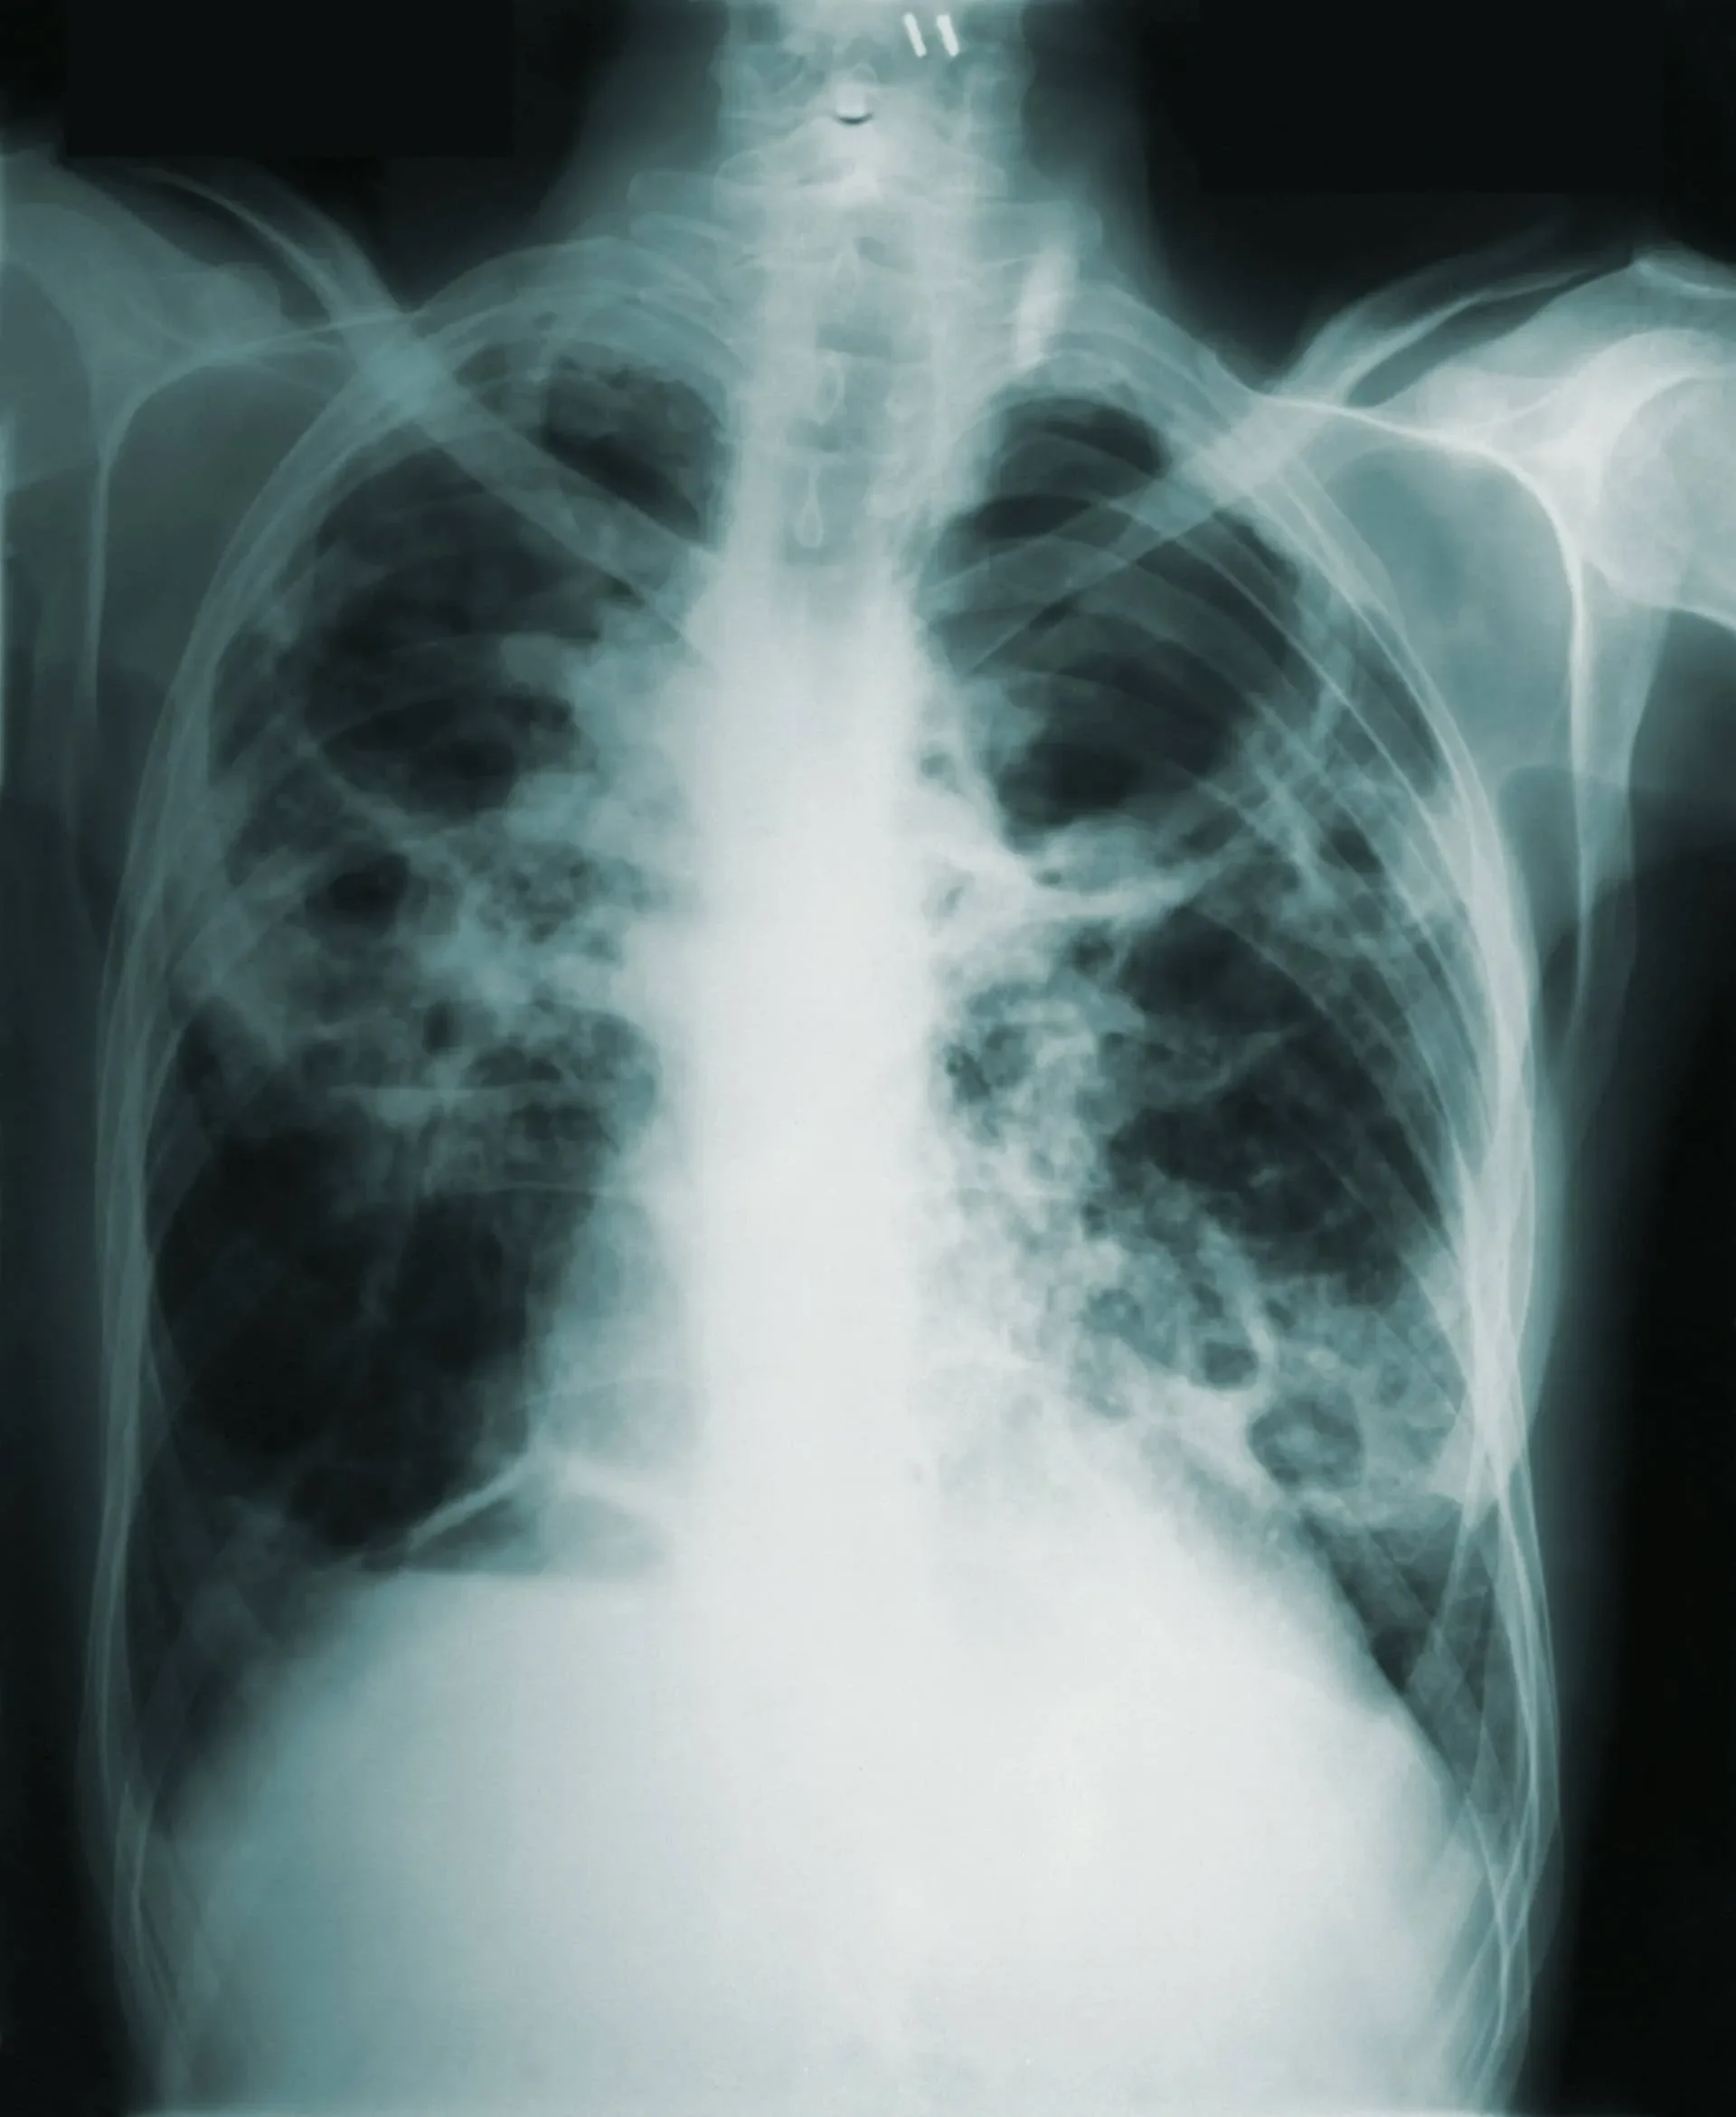

Chest X-ray image showing aspiration pneumonia risk related to untreated swallowing disorders.

The most serious risk of untreated dysphagia is aspiration pneumonia, a lung infection caused when food, liquid, or saliva enters the lungs. Aspiration pneumonia is a leading cause of hospitalization and mortality in older adults and individuals with neurological conditions.

• Recurrent pneumonia or respiratory infections

• Aspiration pneumonia (a leading cause of death in older adults)